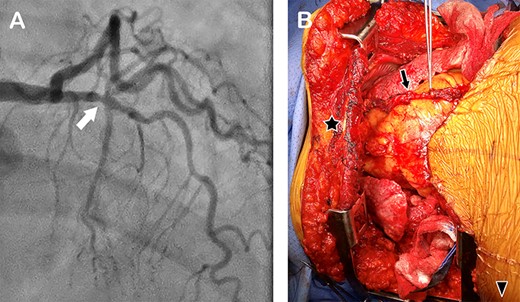

A 71-year-old woman with chronic respiratory failure due to hypersensitivity pneumonitis was evaluated for lung transplantation (LTx) and found to have CAD. Coronary angiogram showed a 70% lesion in the left anterior descending artery (LAD) (Fig. 1A); other coronary arteries had mild disease. We did not recommend coronary artery stenting and the associated dual antiplatelet therapy due to the urgency of her condition. Instead, we listed the patient for either a single right or bilateral LTx with CABG to the LAD. Because the donor’s total lung capacity was much smaller than that of the recipient’s we elected to perform a bilateral LTx with CABG. Due to her previous wedge resection in the right lower lobe and elevated right hemidiaphragm, we anticipated dense adhesion in the posterior diaphragmatic area therefore decided to use the clamshell incision for the lung transplant and CABG with the LITA.

(A) Coronary angiogram showing a stenosis in the left anterior descending artery (arrow); (B) intraoperative photograph of the chest cavity via clamshell incision, showing the harvested LITA lying on the heart (arrow). Star marks the upper sternal edge; arrow head, the patient’s right side.

First, right and left anterolateral thoracotomies at the fourth intercostal spaces were performed (Fig. 2A) and the left and right internal thoracic arteries (RITA) were exposed and freed for 2 cm in both directions. We ligated and divided the RITA, then divided the sternum transversely while preserving the LITA (Fig. 2B). Using a bone hook, we lifted the lower edge of the divided sternum superiorly and anteriorly (so as not to put tension on the LITA) to expose the lower part of the LITA (Fig. 2C). We freed the LITA from the chest wall distally and divided it at the bifurcation after administering 3000 units of heparin intravenously (Fig. 3D). By placing two Finochietto retractors in the right and left fourth intercostal spaces, and using a bone hook to elevate the superior edge of the sternum, we were able to expose and harvest the entire upper portion of the LIMA up to its origin (Fig. 2E). The harvested LIMA (Fig. 1A) was covered with papaverine soaked sponge and tucked in the left pleural cavity for later use.